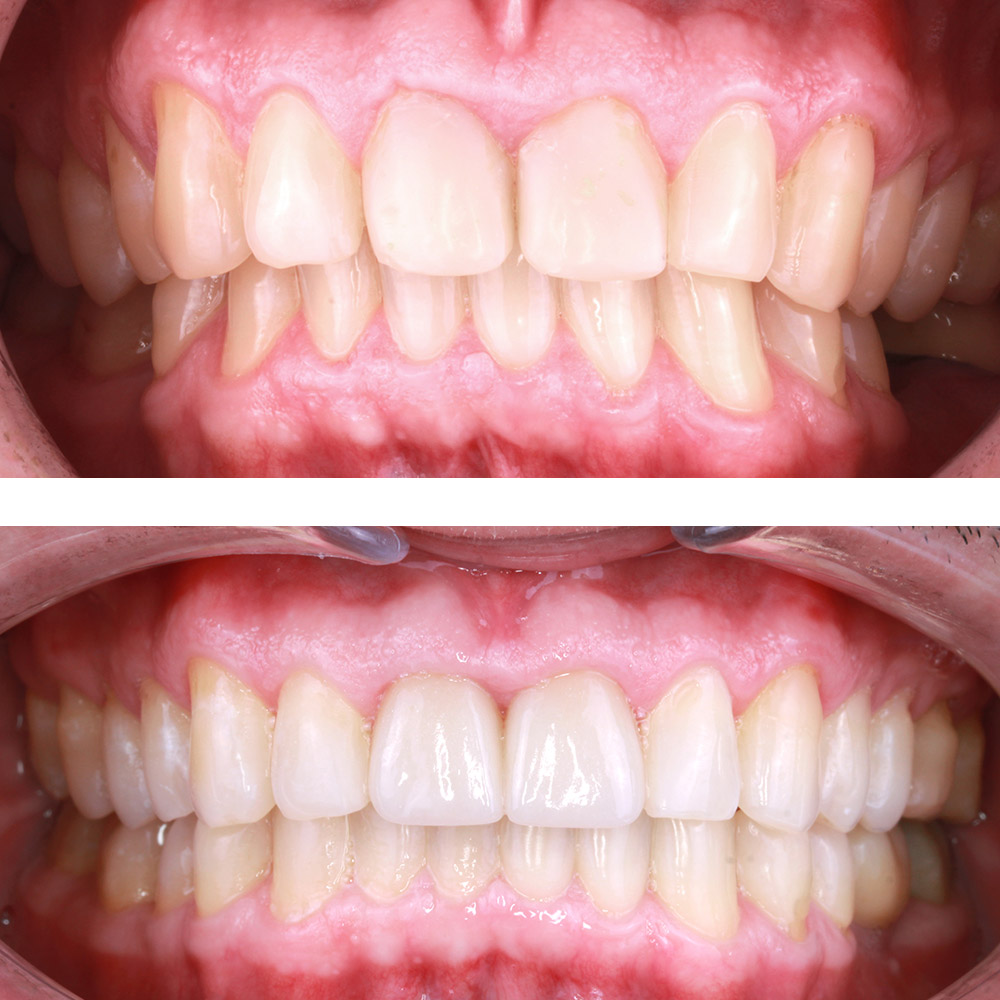

Кейс 12

Бирковская Екатерина Александровна

Количество кап ВЧ 24

Количество кап НЧ 41

ДО

ПОСЛЕ